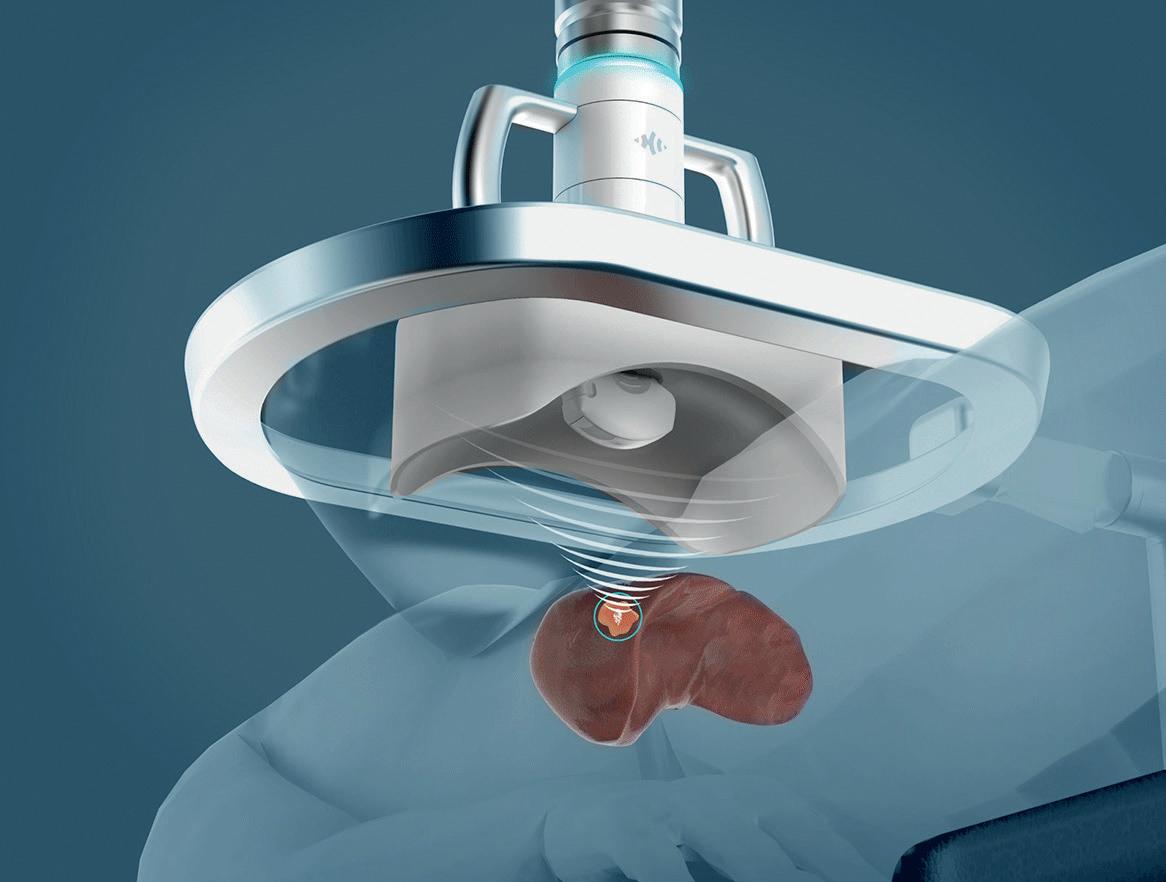

Histotripsy: What we know so far

Mishal Mendiratta-Lala

Histotripsy is a non-thermal, non-ionising and non-invasive focused ultrasound technique which relies on cavitation for mechanical tissue breakdown at the focal point. Leading research into the novel technique, Mishal Mendiratta-Lala (University of Michigan, West Bloomfield, USA)—principal investigator for the #HOPE4LIVER trial evaluating histotripsy in liver tumours— provides a deep dive into the treatment option, discussing its application and evolution in the near future.

In 2024, histotripsy has advanced significantly following its US Food and Drug Administration (FDA) approval in late 2023, allowing many institutions to acquire the technology for clinical use. Most systems were delivered this year, leading to the treatment of over 500 tumours with histotripsy.

Although enthusiasm is high among both patients and the medical community, it is still too early to report definitive new findings. The focus must remain on collecting and analysing data to assess long-term efficacy. A key priority moving forward is careful patient selection, ensuring that histotripsy is used appropriately rather than broadly applying it to all cases.

Histotripsy garners “excitement” in the cancer community

For patients deemed suitable for treatment with histotripsy, the procedure has demonstrated several benefits over alternative ablative techniques. These are largely due to the non-invasive nature of the procedure, minimal bleeding risk, and postprocedure pain and recovery times.

There is excitement in the cancer community about histotripsy’s potential to induce an abscopal response— a systemic immune reaction against cancer. However, this effect has not been reliably observed in clinical practice yet and we look forward to emerging research that may bear out evidence of this response.

Current data supporting histotripsy’s efficacy is limited but promising. To date,

there are two peer-reviewed studies that are analysing histotripsy—the first-in-man THERESA trial evaluating histotripsy of hepatic tumours, and the #HOPE4LIVER trial which concerns the treatment of liver tumours with histotripsy. The former is a small early study focused solely on safety. The 36-hour data confirmed that treated volumes were effectively ablated, demonstrating initial safety. The latter #HOPE4LIVER trial involved 44 tumours, and evaluated 30-day safety and efficacy. The results showed that histotripsy successfully treated the target lesions, with no enhancement of the treated tumours, confirming shortterm efficacy.

These studies confirm that histotripsy is safe, but long-term efficacy, survival benefits, and recurrence rates remain unknown. To determine whether histotripsy improves overall survival and delays disease recurrence, more clinical trials and data-sharing across institutions are essential. Treating patients with only 30-day data in 44 tumours is premature for broad clinical adoption, emphasising the need for

further research.

“Challenging” operator learning curve

Leading histotripsy technology innovation, the Edison (HistoSonics) platform has a notable operator learning curve due to its complexity and multiple components requiring proficiency. Challenges include setting up the water bath correctly to prevent leaks, accurately identifying the target, and properly defining treatment boundaries. The robotic head’s large and bulky design adds difficulty in positioning for optimal lesion treatment. Additionally, treatment limitations arise from factors such as lesion depth, adjacent structures, and device voltage constraints.

As for institutional implementation, while the platform can be highly effective when the target is appropriately selected, its adoption requires significant training, experience, and institutional investment in both personnel and infrastructure. Proper

With more institutions purchasing the device, the accumulation of clinical data will be crucial. However, the success of histotripsy will depend on strong collaboration within the clinical community to analyse outcomes and refine patient selection criteria. Not all patients will be ideal candidates, making ongoing clinical trials essential for optimising the technology’s impact in cancer treatment.

Global adoption of histotripsy is likely to grow, but its integration into standard care will require further validation through research. We need more clinical trials with combination therapies and we need more trials looking at treatment of different cancer types.

A key focus for 2025 will be ensuring that histotripsy is implemented effectively and safely. Additionally, while the potential for an abscopal response is intriguing, it remains unproven in patients, and caution is necessary to avoid unintended consequences.

There is excitement in the cancer community about histotripsy’s potential to induce an abscopal response—a systemic immune reaction against cancer”

training programmes and support are essential for successful integration.

I believe a successful histotripsy programme requires institutional commitment and resources, making it challenging to adopt easily.

While institutions can integrate the technology, its success will depend on the presence of a strong clinical team, institutional support, a general anaesthesia team, adequate space and finally, a financial bolster. Insurance reimbursement is not always guaranteed, and thus institutions will need a strong financial team to navigate funding and advocate for coverage.

What’s to come for histotripsy in 2025

The year 2025 will be an exciting one for histotripsy as the field evolves.

In addition, histotripsy is being expanded to renal and pancreas applications which will be very exciting. Overall, histotripsy has significant promise, and 2025 will be a pivotal year in determining its role in the broader clinical landscape. The medical community plays a critical role in shaping the clinical narrative and ensuring responsible treatment decisions. Looking ahead, I hope to be able to lead clinical trials, which will be essential in identifying the ideal patient population and determining whether histotripsy can provide meaningful survival benefits for cancer patients.